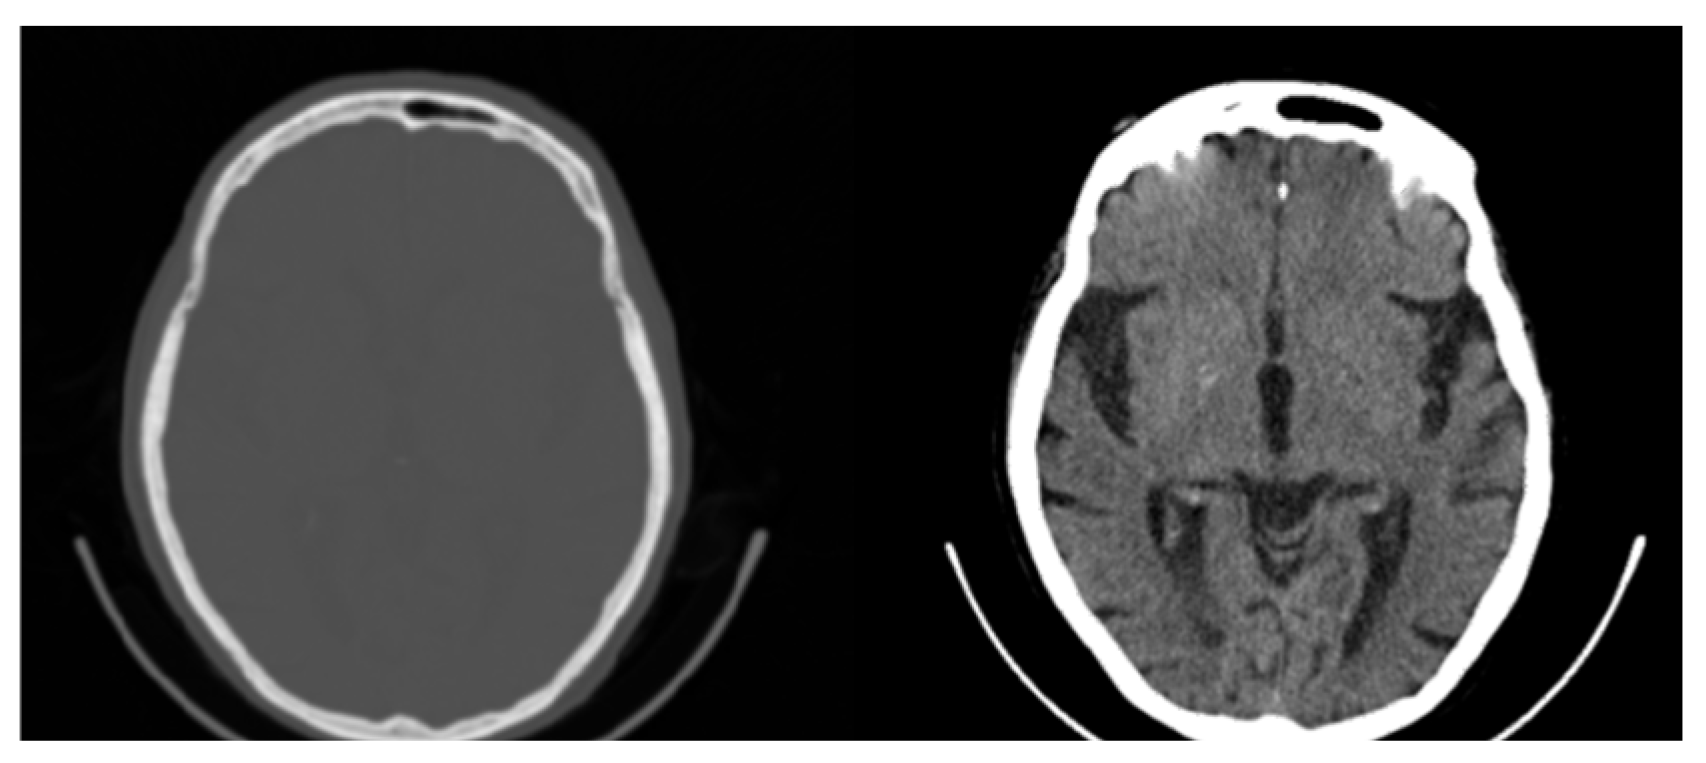

2. Materials and Methods

3.1. CIT Application

3.2. Colormap Folding Application